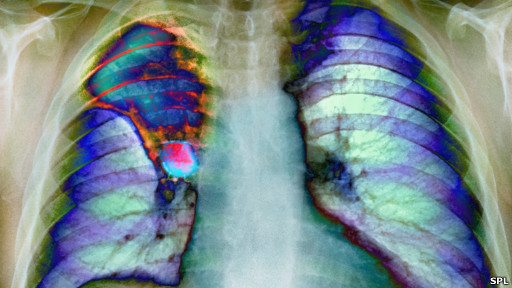

發表在《英國癌症》雜誌上的研究報告指出,這或許部分解釋了為什麼英國的醫療技術和儀器設備先進,而癌症患者存活率卻比其他發達國家低。